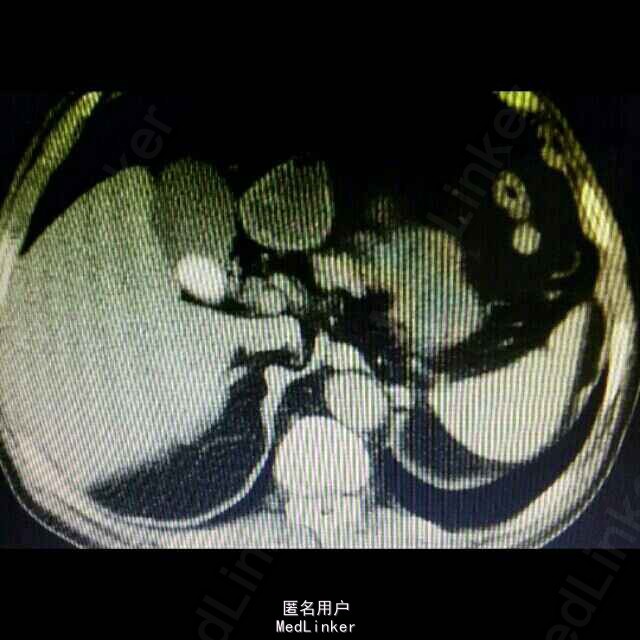

1、 主诉:上腹部疼痛4年余,加重2月。 2、 现病史:患者4年前无明显诱因出现上腹间歇性胀痛,可忍受,伴反酸、恶心、无呕吐,未予以治疗。患者2月前上腹部通天症状加重,伴肩部放射痛,伴反酸、恶心、无呕吐,未予以治疗。患者15天前因“感冒”就诊于当地医院行胸部CT示:肝左叶胆管结石并肝内胆管扩张、肝左叶萎缩。今患者为进一步治疗,前来我院就诊,门诊以“胆囊结石并急性胆囊炎”收入院,患者自发病以来精神状态可、食欲差,睡眠良好,大、小便正常,体重无明显变化。

3、 辅助检查:上腹部 CT平扫示:肝左叶胆管结石并肝内胆管扩张、肝左叶萎缩。胆囊结石,双肾囊肿。